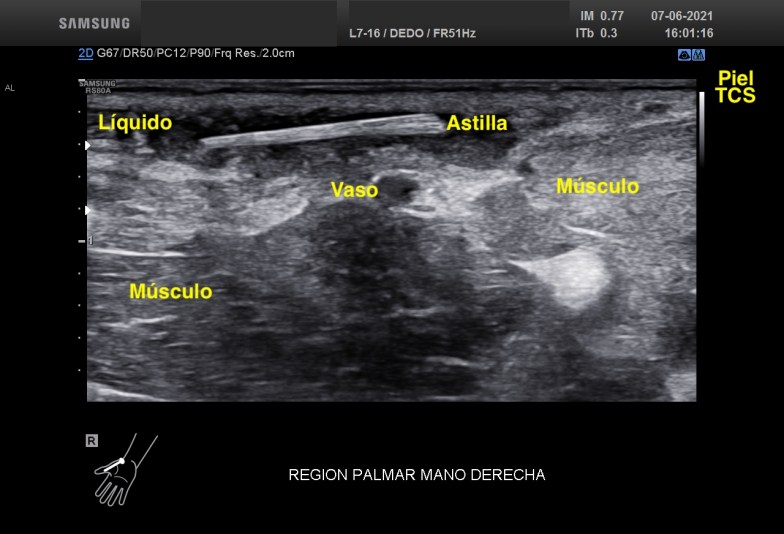

En este momento nos hace falta claramente la anatomía, saber perfectamente donde está alojada la ecoestructura o cuerpo extraño que está provocando claramente una reacción a cuerpo extraño. Se demuestra que la situación es subcutánea, no afecta a vasos y no afecta al tejido muscular. En el Tejido Celular Subcutáneo existe claramente cambios en la ecoarquitectura normal de la región, con presencia de líquido y aumento global de las partes blandas del tejido graso. El líquido parece estar floculado, es espeso y además no es anecoico, con lo que podríamos estar delante de algún tipo de infección local que se confirmó tras la extirpación del cuerpo extraño y que precisó tratamiento antibiótico y que queda demostrado en la imagen 3 y la imagen 4.

La imagen 5 y 6 te la pongo para que puedas ver como es el tejido afecto con el tejido conservado normal. Son Comparativos. Como la ecoestructura normal del TCS está respetado e integro. La musculatura y los vasos comparados y documentados con sus respectivos pictogramas.